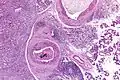

Very high mag.

Their histologic appearance is similar to ductal breast carcinoma.